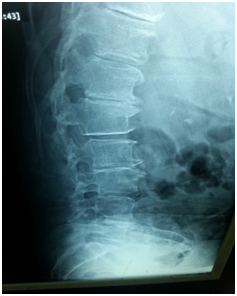

Flat back syndrome

- Loss of Lumbar Lordosis.

- Need an extensive release of the posterior elements with facet joints osteotomy.

- Anterior release MAY also be needed in severely rigid curves.

- Anterior column reconstruction with cages especially at Lumbo- sacral junction is necessary and always required to restore sagittal balance (Figure 3).

Figure 3 Flat back syndrome.